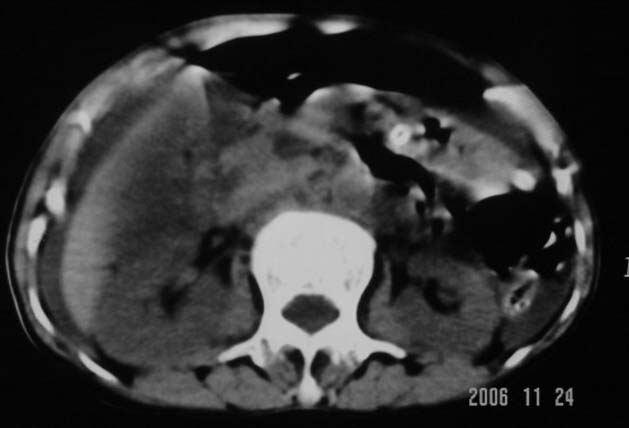

仰卧位见:肝前间隙及肝脾间隙内可见新月形气体密度影,边缘清楚,侧卧位见气体随体位改变而移动,ct值约-929hu。膈下、肝下间隙及部分肠间隙可见液性密度影。考虑:1、上腹部空腔脏器穿孔,以胃穿孔可能性大。2、少量腹水。

仰卧位见:肝前间隙及肝脾间隙内可见新月形气体密度影,边缘清楚,侧卧位见气体随体位改变而移动,ct值约-929hu。膈下、肝下间隙及部分肠间隙可见液性密度影。考虑:1、上腹部空腔脏器穿孔,结合临床,首先考虑胃穿孔可能性大。2、少量腹水

补充--肝门及肝肾间隙以见积气显示。

支持消化道空腔脏器穿孔(腹腔内大量游离气体影,小网膜囊内亦见气体影),少量腹水。